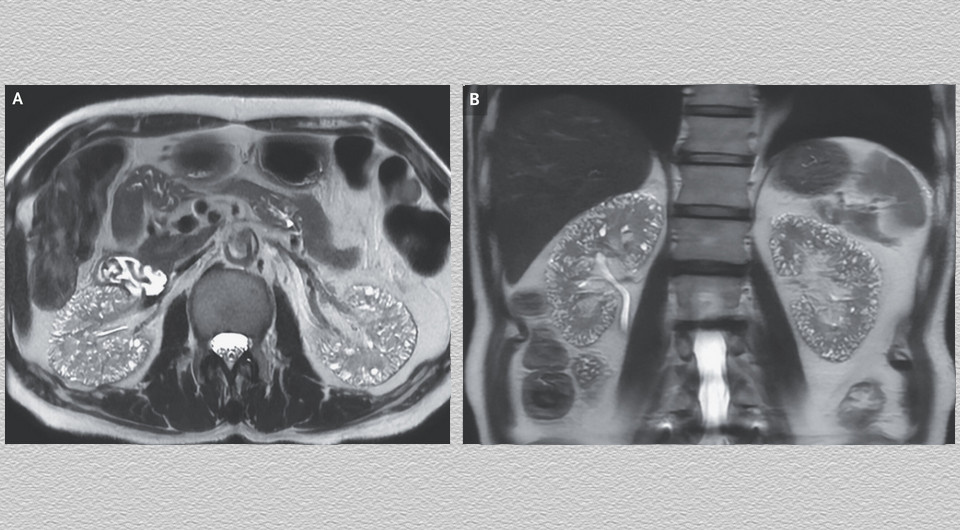

В китайскую клинику поступил 60-летний мужчина с артериальной гипертензией и биполярным расстройством для прохождения МРТ по поводу симптомов со стороны нижних отделов мочевыводящих путей. Он в течение 17 лет принимал препараты лития для стабилизации настроения, которые отменили за год до этого из-за ухудшения функции почек (уровень креатинина в сыворотке крови возрос до 159 при норме 53–115 микромоль на литр). В семейном анамнезе пациента не было кистозных поражений почек. На Т2-взвешенной МРТ у него визуализировались многочисленные микрокисты в корковом и мозговом веществе обеих почек. Врачи Чжэнхун Ляо (Cheng-Hung Liao) и Гаолан Лю (Kao-Lang Liu) из Тайваньской национальной университетской больницы описали случай в The New England Journal of Medicine.

На основании данных анамнеза и обследования мужчине поставили диагноз микрокист на фоне нефропатии, вероятно вызванной литием. Литий может производить различные токсические эффекты на почки, включая нефрогенный несахарный диабет, почечный канальцевый ацидоз и хроническую тубулоинтерстициальную нефропатия. При последней в почках могут появляться множественные кисты размером 1–2 миллиметра, видимые при лучевой диагностике. Пациенту продолжили лечение биполярного расстройства альтернативными препаратами. В течение двух последующих лет наблюдения его почечная функция оставалась стабильной.